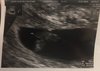

Dziewczyny, wracam z wizyty. Plamienia nie są groźne. Wszystko ok :) serduszko bije, nie ma krwiaka, dzidzia rośnie jak na drożdżach, ma już 0,95cm. Mam się oszczędzać i dalej brać duphaston i luteinę a w tyg zrobie wyniki progesteronu, wyślę jej smsem i zobaczy czy zmniejszyć czy zwiększyć dawki. Ogolnie się uspokoiłam i jestem zadowolona :) załączam foto.

Załączniki

• 9BD0B9A3-AAA8-4277-B21A-85CFFBA70B5D.jpeg

9BD0B9A3-AAA8-4277-B21A-85CFFBA70B5D.jpeg

1 MB · Wyświetleń: 112